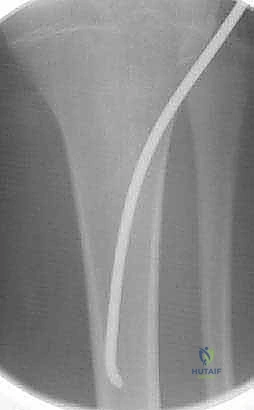

- المسامير النخاعية المرنة (Flexible Intramedullary Nails - TENs): وهي تقنية حديثة ومثالية للأطفال. يتم إدخال مسامير مرنة من التيتانيوم داخل تجويف العظم عبر شقوق صغيرة جداً (Minimally Invasive). تعمل هذه المسامير كدعامة داخلية تسمح للعظم بالالتئام بسرعة دون فتح جراحي كبير، وتوفر ثباتاً ممتازاً.

- استخدام جهاز الأشعة القوسي (C-Arm Fluoroscopy): يُستخدم هذا الجهاز المتطور طوال العملية لتوفير صور أشعة حية ومباشرة، مما يسمح للدكتور هطيف برؤية العظم من الداخل دون الحاجة لشقوق جراحية كبيرة.

- تمرير المسامير والتثبيت: يتم إدخال المسامير المرنة بمهارة فائقة داخل تجويف العظم وتوجيهها لتتجاوز منطقة الكسر، مما يعيد العظم إلى استقامته الطبيعية ويثبته بقوة.